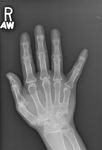

CT findings of severe basal ganglia calcification in a patient with pseudohypoparathyroidism

From the collection of Kent Wehmeier, University of Florida Jacksonville